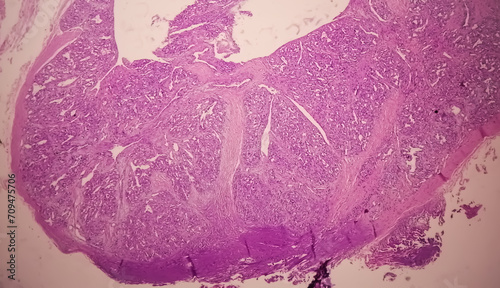

Mikrofotografi - Plakater, Poster, Billeder på lærred